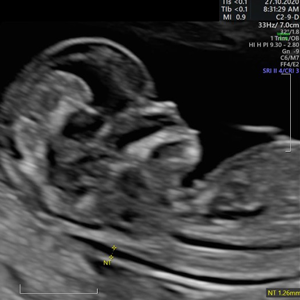

Dr. Homero Flores Tamez

Ginecología y Obstetricia

Medicina Materno Fetal

- Instituto Nacional de Perinatología

- Pionero en México en ofrecer diagnóstico por ultrasonido dentro del consultorio, así como en incorporar tecnología 3D y Doppler.